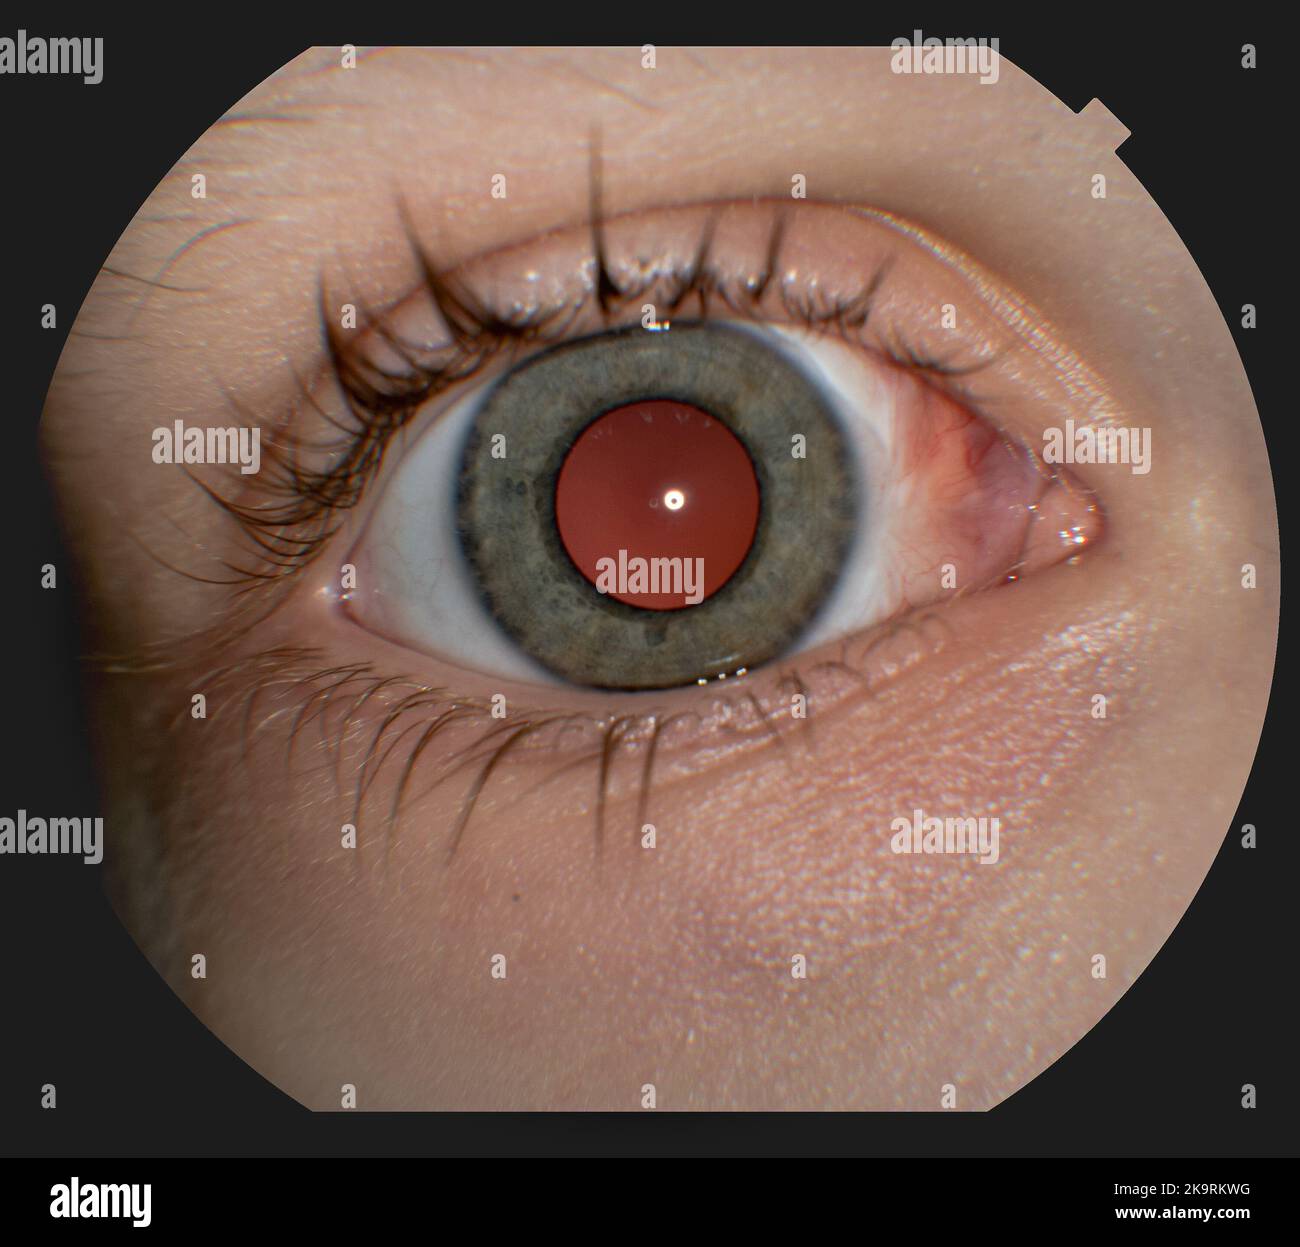

Fundus: routine examination established by an ophthalmoscope to check the health of the eye. Stock Photohttps://www.alamy.com/image-license-details/?v=1https://www.alamy.com/fundus-routine-examination-established-by-an-ophthalmoscope-to-check-the-health-of-the-eye-image476923031.html

Fundus: routine examination established by an ophthalmoscope to check the health of the eye. Stock Photohttps://www.alamy.com/image-license-details/?v=1https://www.alamy.com/fundus-routine-examination-established-by-an-ophthalmoscope-to-check-the-health-of-the-eye-image476923031.htmlRF2JKWM5B–Fundus: routine examination established by an ophthalmoscope to check the health of the eye.